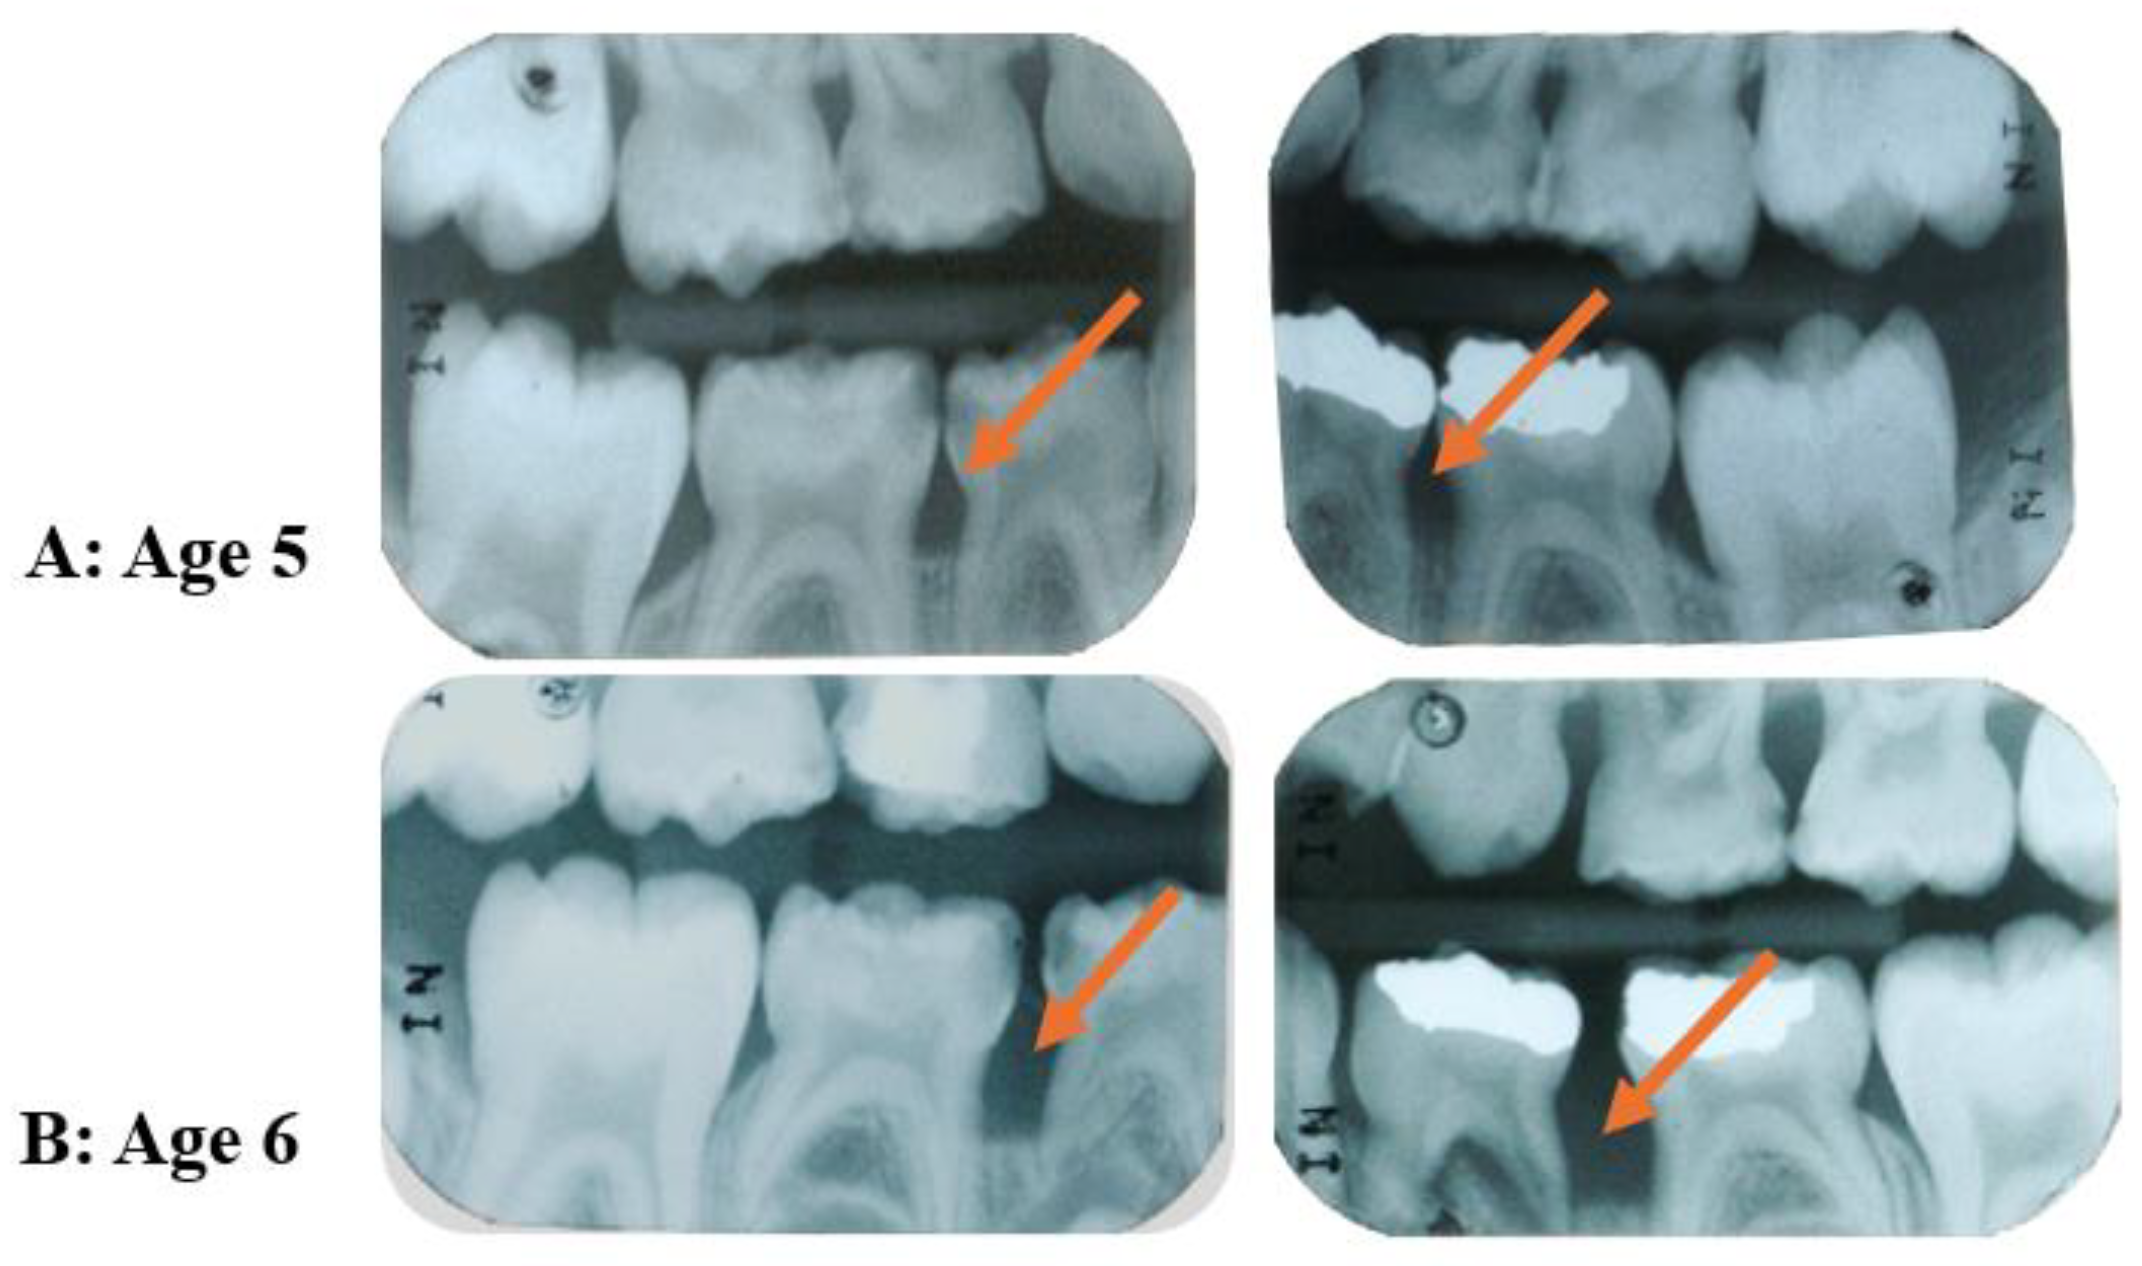

- Bimstein, E. Radiographic Description of the Distribution of Aggressive Periodontitis in Primary Teeth. J. Clin. Pediatr. Dent. 2018, 42, 91–94. [Google Scholar] [CrossRef] [PubMed]

- Jensen, A.B.; Ennibi, O.K.; Ismaili, Z.; Poulsen, K.; Haubek, D. The JP2 Genotype of Aggregatibacter Actinomycetemcomitans and Marginal Periodontitis in the Mixed Dentition. J. Clin. Periodontol. 2016, 43, 19–25. [Google Scholar] [CrossRef] [PubMed]

- Koo, S.S.; Fernandes, J.G.; Li, L.; Huang, H.; Aukhil, I.; Harrison, P.; Diaz, P.I.; Shaddox, L.M. Evaluation of Microbiome in Primary and Permanent Dentition in Grade C Periodontitis in Young Individuals. J. Periodontol. 2024; Epub ahead of print. [Google Scholar] [CrossRef]